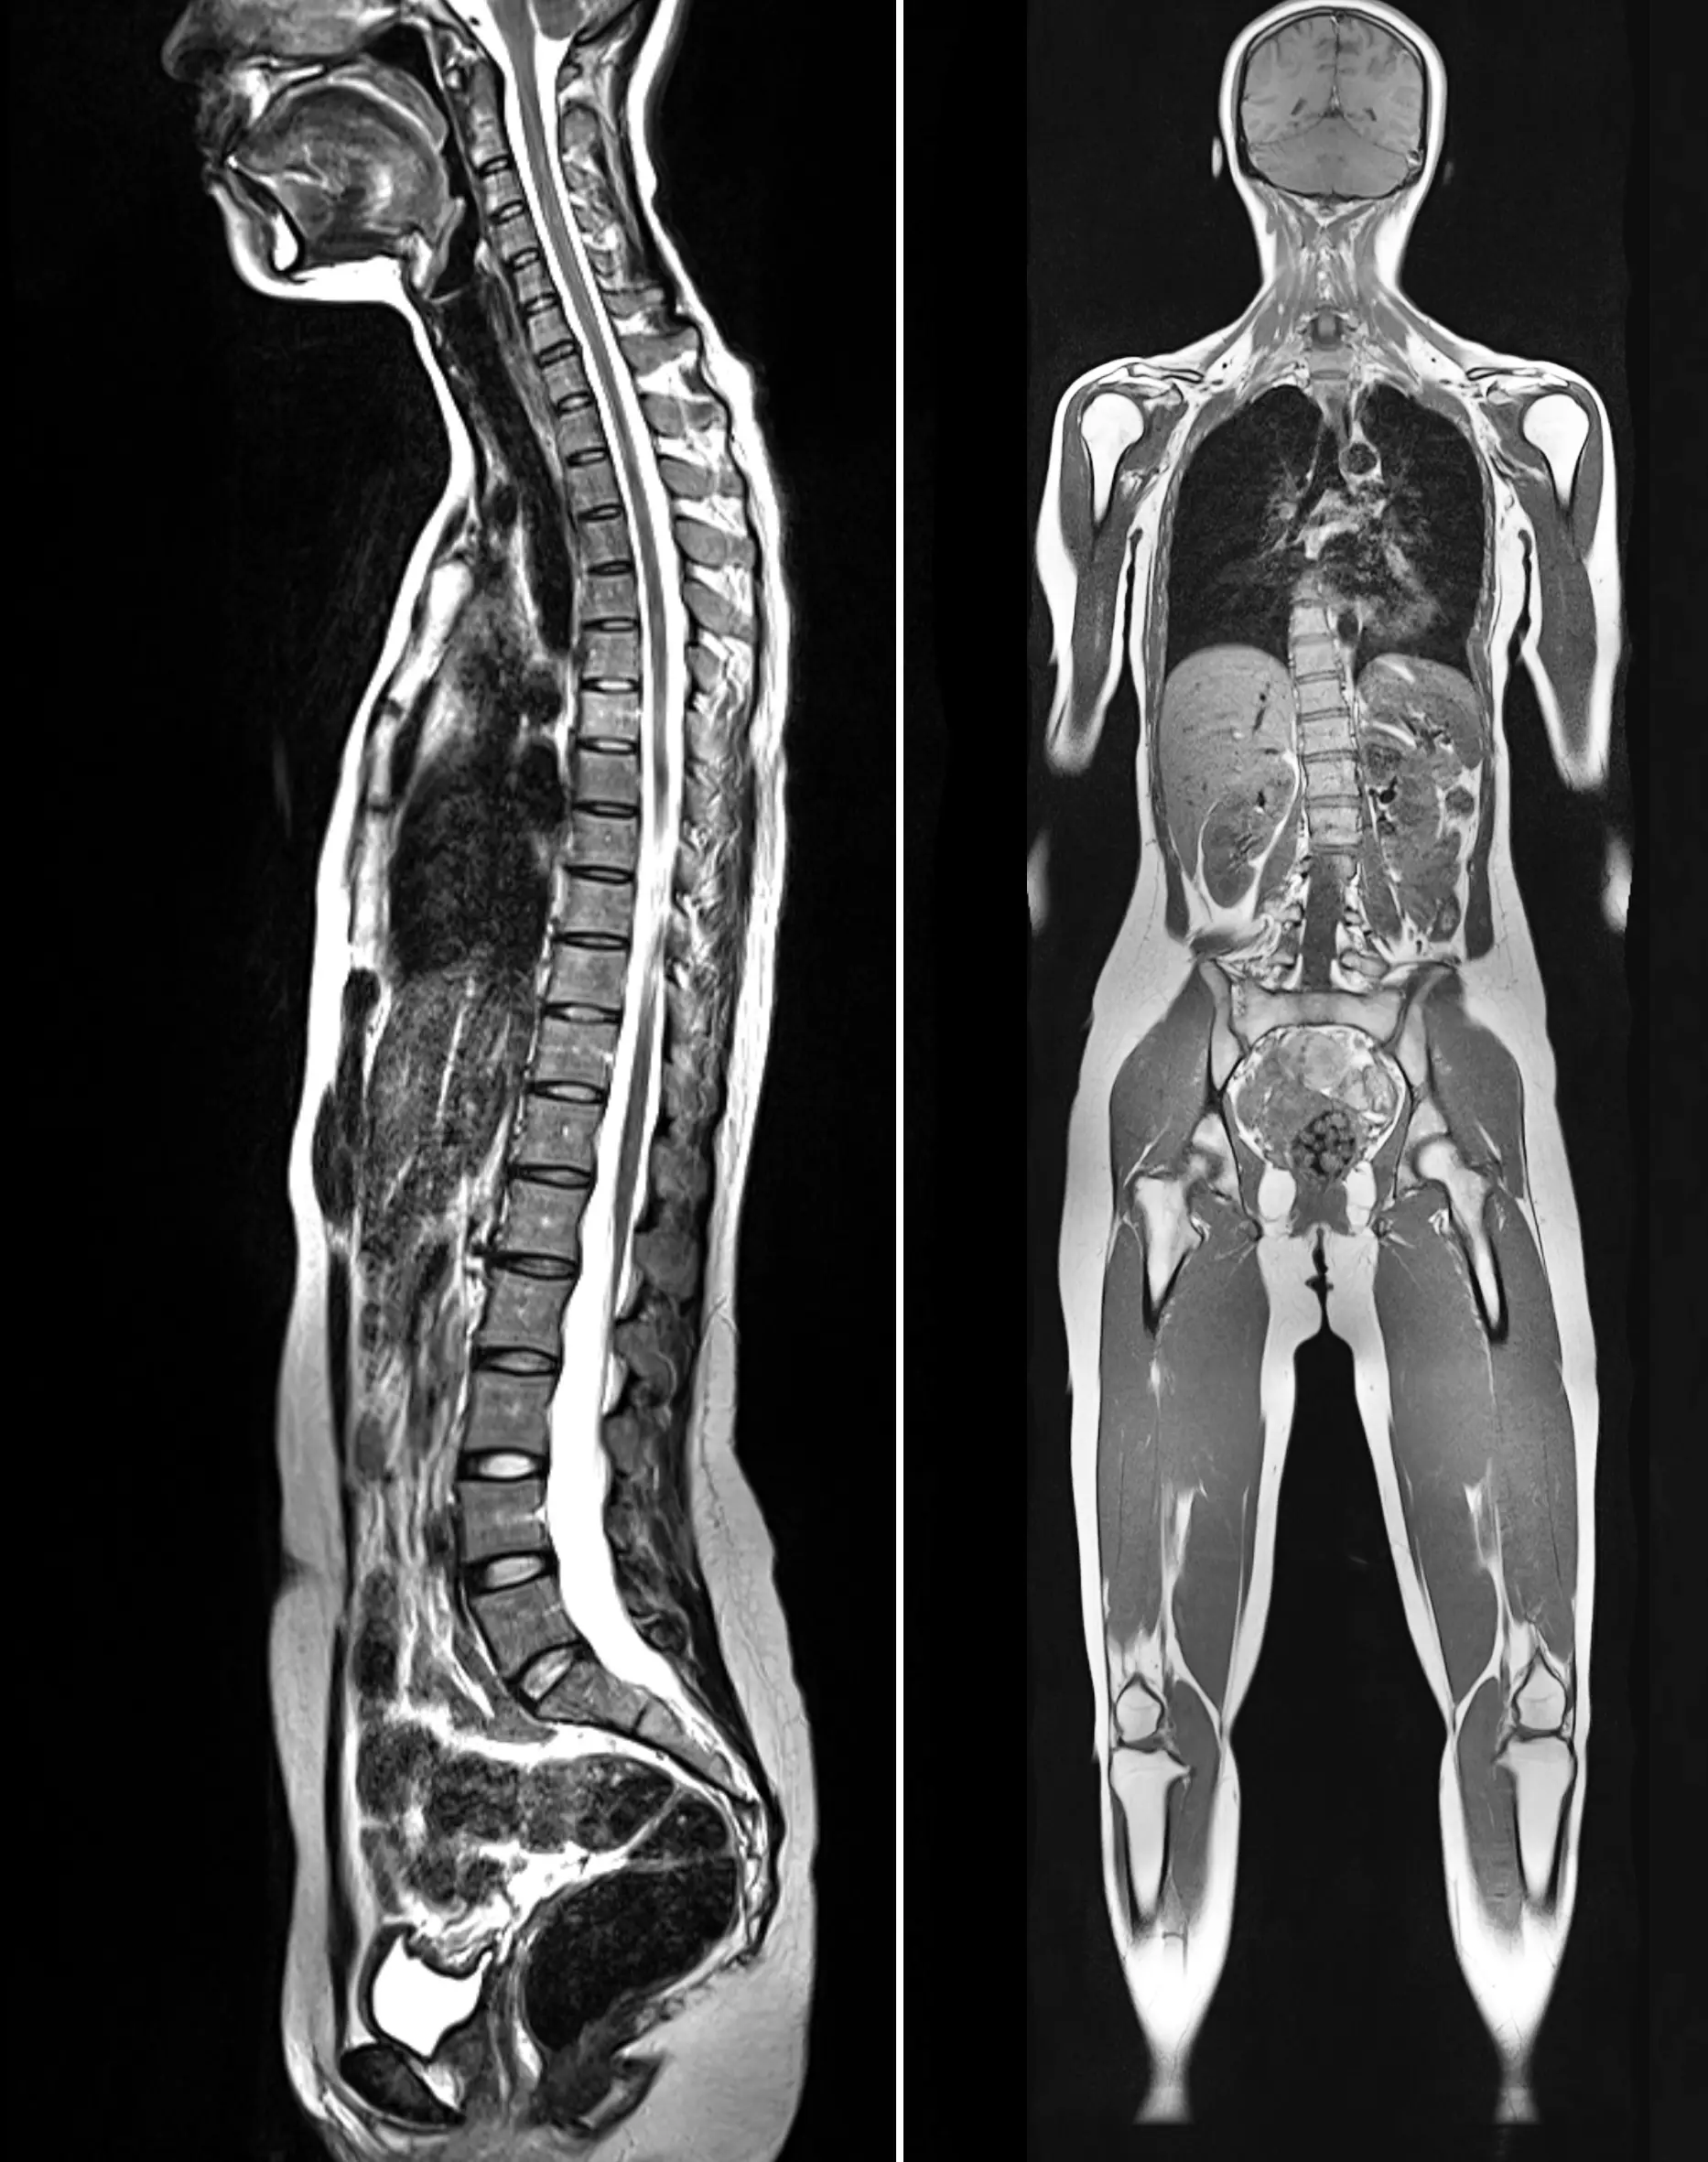

МРТ мягких тканей (любая область)